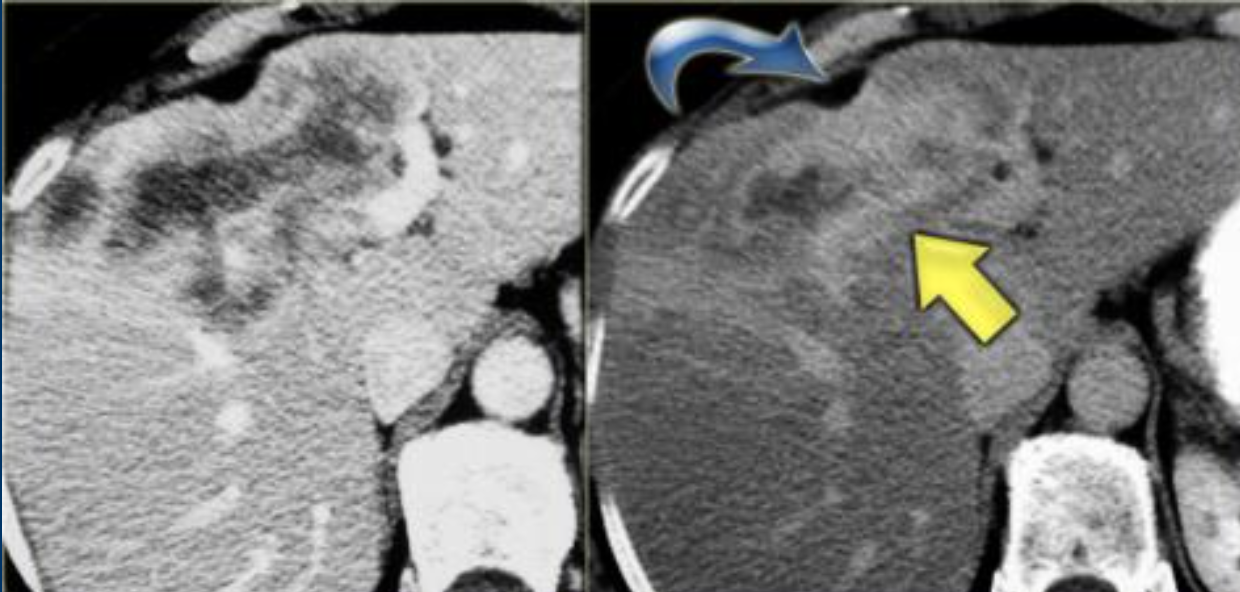

Imaging findings of Intrahepatic Cholangiocarcinoma

where geographically is it more common?

- More common in asia than in the USA

- Adenocarcinoma from the intrahepatic bile ducts

- Biliary ductal dilatation distal to tumour

- lesions have irregular borders with infiltrative margins

- Delayed peripheral to central enhancement as a result of fibrosis and hypovascularity

- Capsular retraction and vascular invasion.